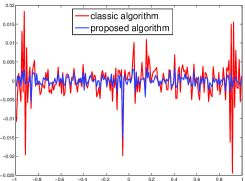

Noiseless projection data: Since the ghost in this phantom is invisible at 22 directions [10, 11], the reconstruction images usually suffer from artifacts. in our simulations, the projection data were collected in 112 and 82 directions: 90 and 60 with equal angle increments from to and 22 specified views in which the ghost is invisible [10]. Iteration procedures were terminated when for the noiseless projections.

The reconstruction images from the noiseless projection data were shown in the Fig. 6. For comparison, Table 3 present the iterations, MSE, Res and running time(RT) of different reconstruction results.

|

|

| TV-S | TV-S |

|

|

| TV-PPS | TV-PPS |

Noised projection data: For the noised projection data, the iteration processes were terminated when for 82 and 112 projections. The reconstruction images were given in Fig. 7. Table 4 showed the MSEs, iterations and running time of program of the results of images in Fig. 7.

|

|

| TV-S | TV-S |

|

|

| TV-PPS | TV-PPS |

By comparing the images in Fig. 6, 7 and numbers in Table 3, 4, we can obtain the same conclusions that the proposed perturbation can not only improve qualities of reconstructed images, but also can accelerate the convergent speed. However, we can observe that the reconstruction images suffer from artifacts regardless of the classic and the proposed algorithm when the projections is inadequate.